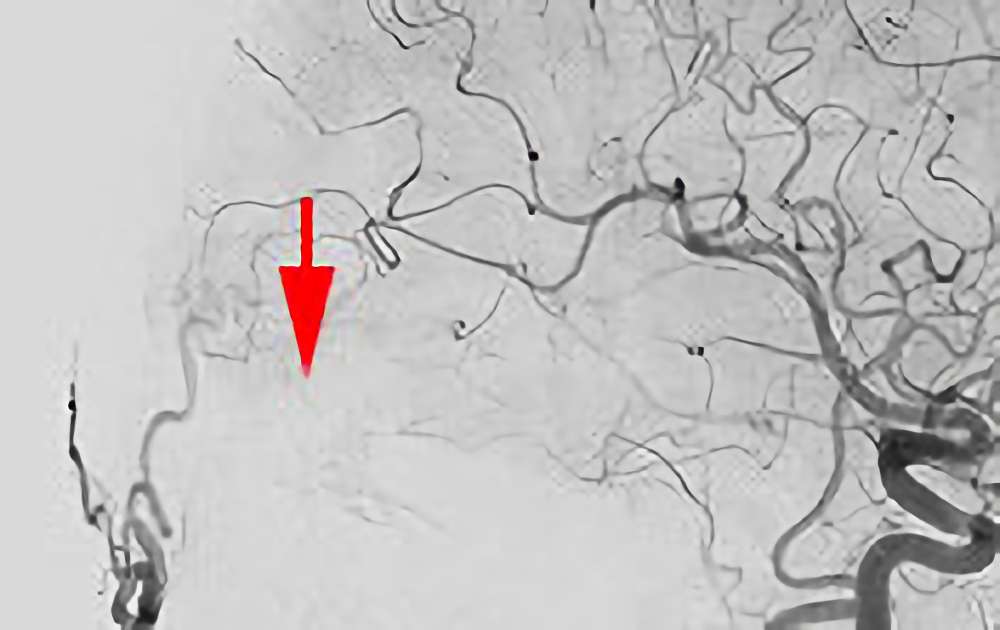

症例 '20年7月

No.

860

'20年7月21日

硬膜動静脈瘻

40代

院内外来

手術写真